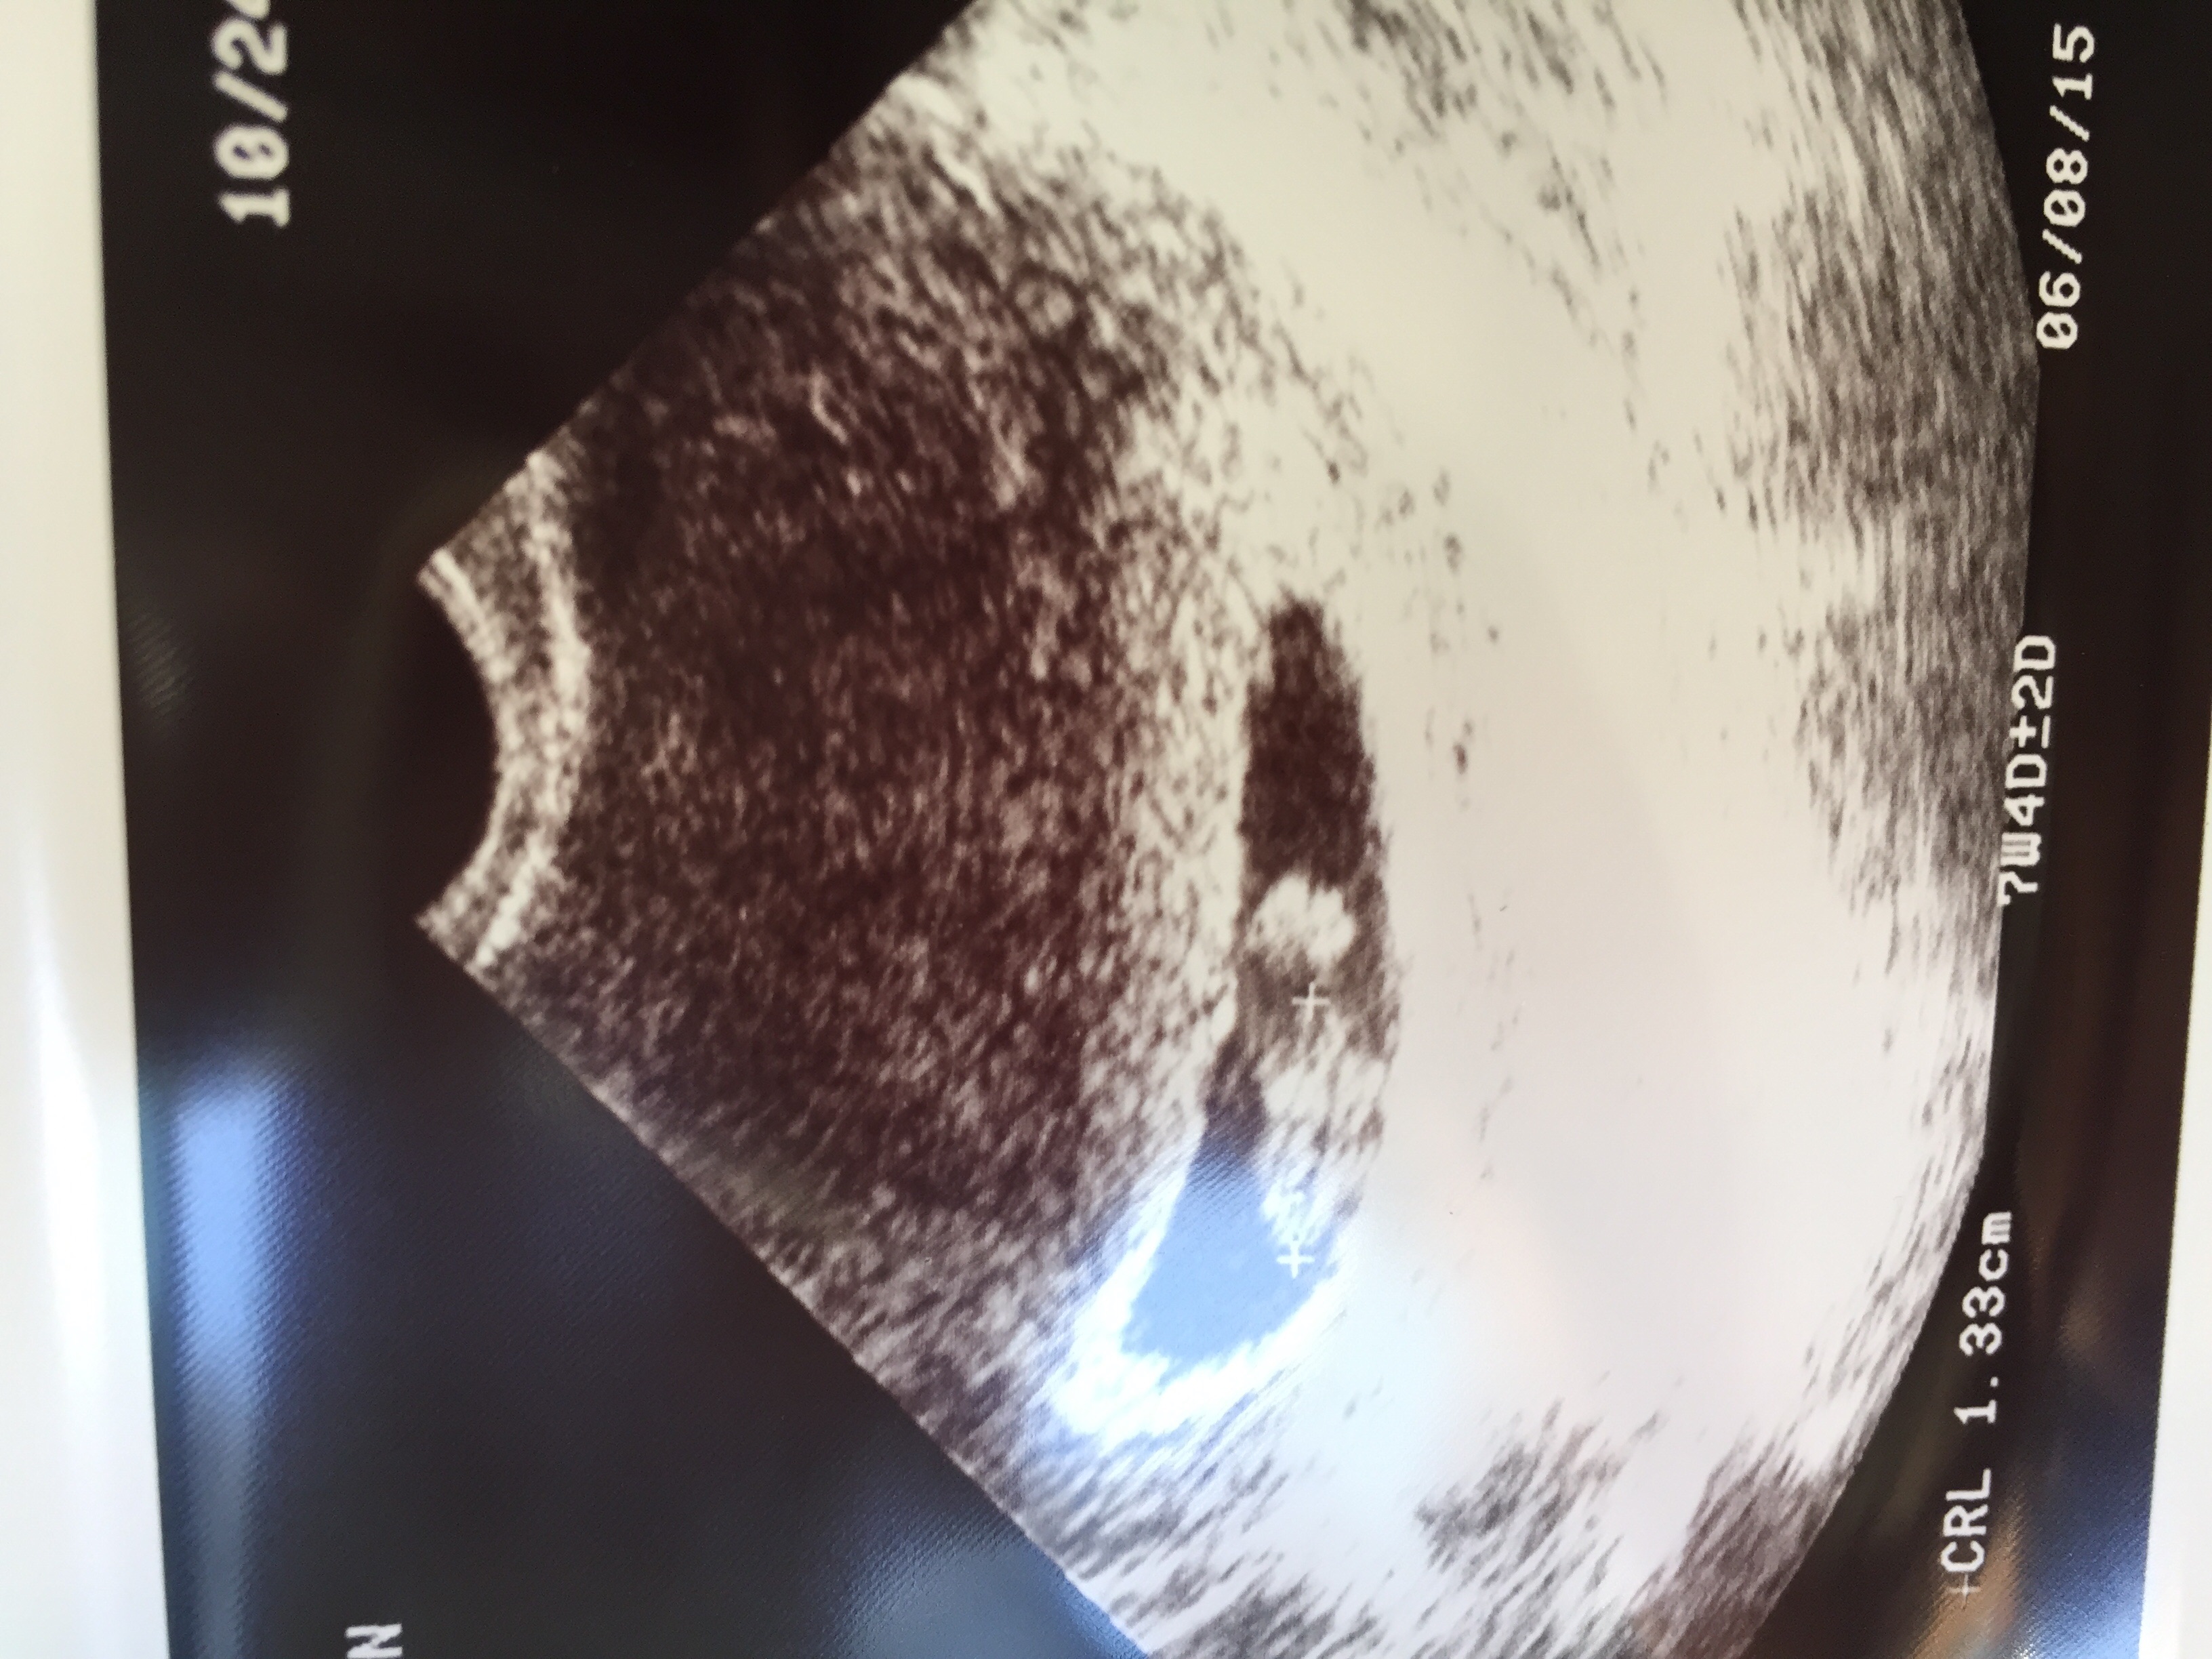

This is mine, went in 10-22 for an 8 week appointment (Kaiser Permanente insurance) turned out to be 7 weeks so I have to go back in for an "official" US on 11-3, but they still gave me a printout of my little McNugget! Seeing the heartbeat on the screen was my light bulb; I suffer from a chronic illness that makes me experience constant nausea, stomach pain and exhaustion (basically preggo without the fun prize in 9 months) so I didn't "feel" pregnant. Watching that flutter, it finally sank in.